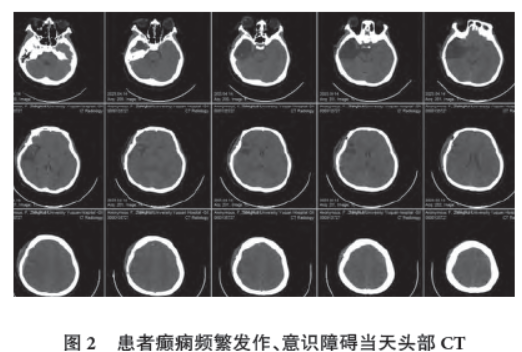

逐渐好转,并且动态复查视频脑电图。癫痫频繁发作、意识障碍

当天,脑电图左侧半球低至中波幅4~6 Hz θ 活动,右侧半球电压减低(图1),头部电子计算机断层扫描(Computed tomography,CT)见右侧颞区切除术后改变,弥漫性脑水肿,脑沟变浅(图2)。